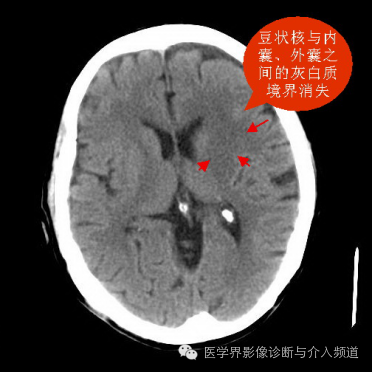

傳說中腦梗塞在24h內(nèi)是CT的盲區(qū),但隨著CT分辨率的提高,一些征象越來越受到重視,通過正確判斷這些征象,我們可以作出超急性期腦梗塞的診斷。 1、灰白質(zhì)境界模糊,最早見于梗塞后3-6小時(shí),尤其是大血管閉塞時(shí)。 2、腦溝消失:腦梗塞發(fā)生數(shù)小時(shí)后,腦組織出現(xiàn)細(xì)胞性水腫、血管源性水腫,腦溝消失可出現(xiàn)在灰質(zhì)-白質(zhì)境界不清之前。 3、島帶消失:是大腦中動脈梗塞最早的征象。島帶包括島葉外側(cè)的灰白質(zhì)束、屏狀核、外囊,CT上表現(xiàn)為低密度、局部灰白質(zhì)分界消失。 4、動脈高密度征:最常見為大腦中動脈、基底動脈閉塞,CT值 77~89 Hu( 正常42~53 Hu ),動脈密度增高與腔內(nèi)血栓有關(guān)。 5、豆?fàn)詈四:阂彩谴竽X中動脈閉塞的早期征象,豆?fàn)詈伺c內(nèi)囊、外囊之間的灰白質(zhì)境界消失,輪廓模糊或密度減低。 當(dāng)然患者的癥狀和體征是首先必須觀察的,急診CT的時(shí)候,我們可以在擺位時(shí)候做個(gè)簡單的病史采集和體格檢查,臨床與影像需要互相印證,任何影像征象都需要臨床的支持。如果臨床癥狀明顯,CT未見異常,建議MR檢查,或者24小時(shí)復(fù)查。